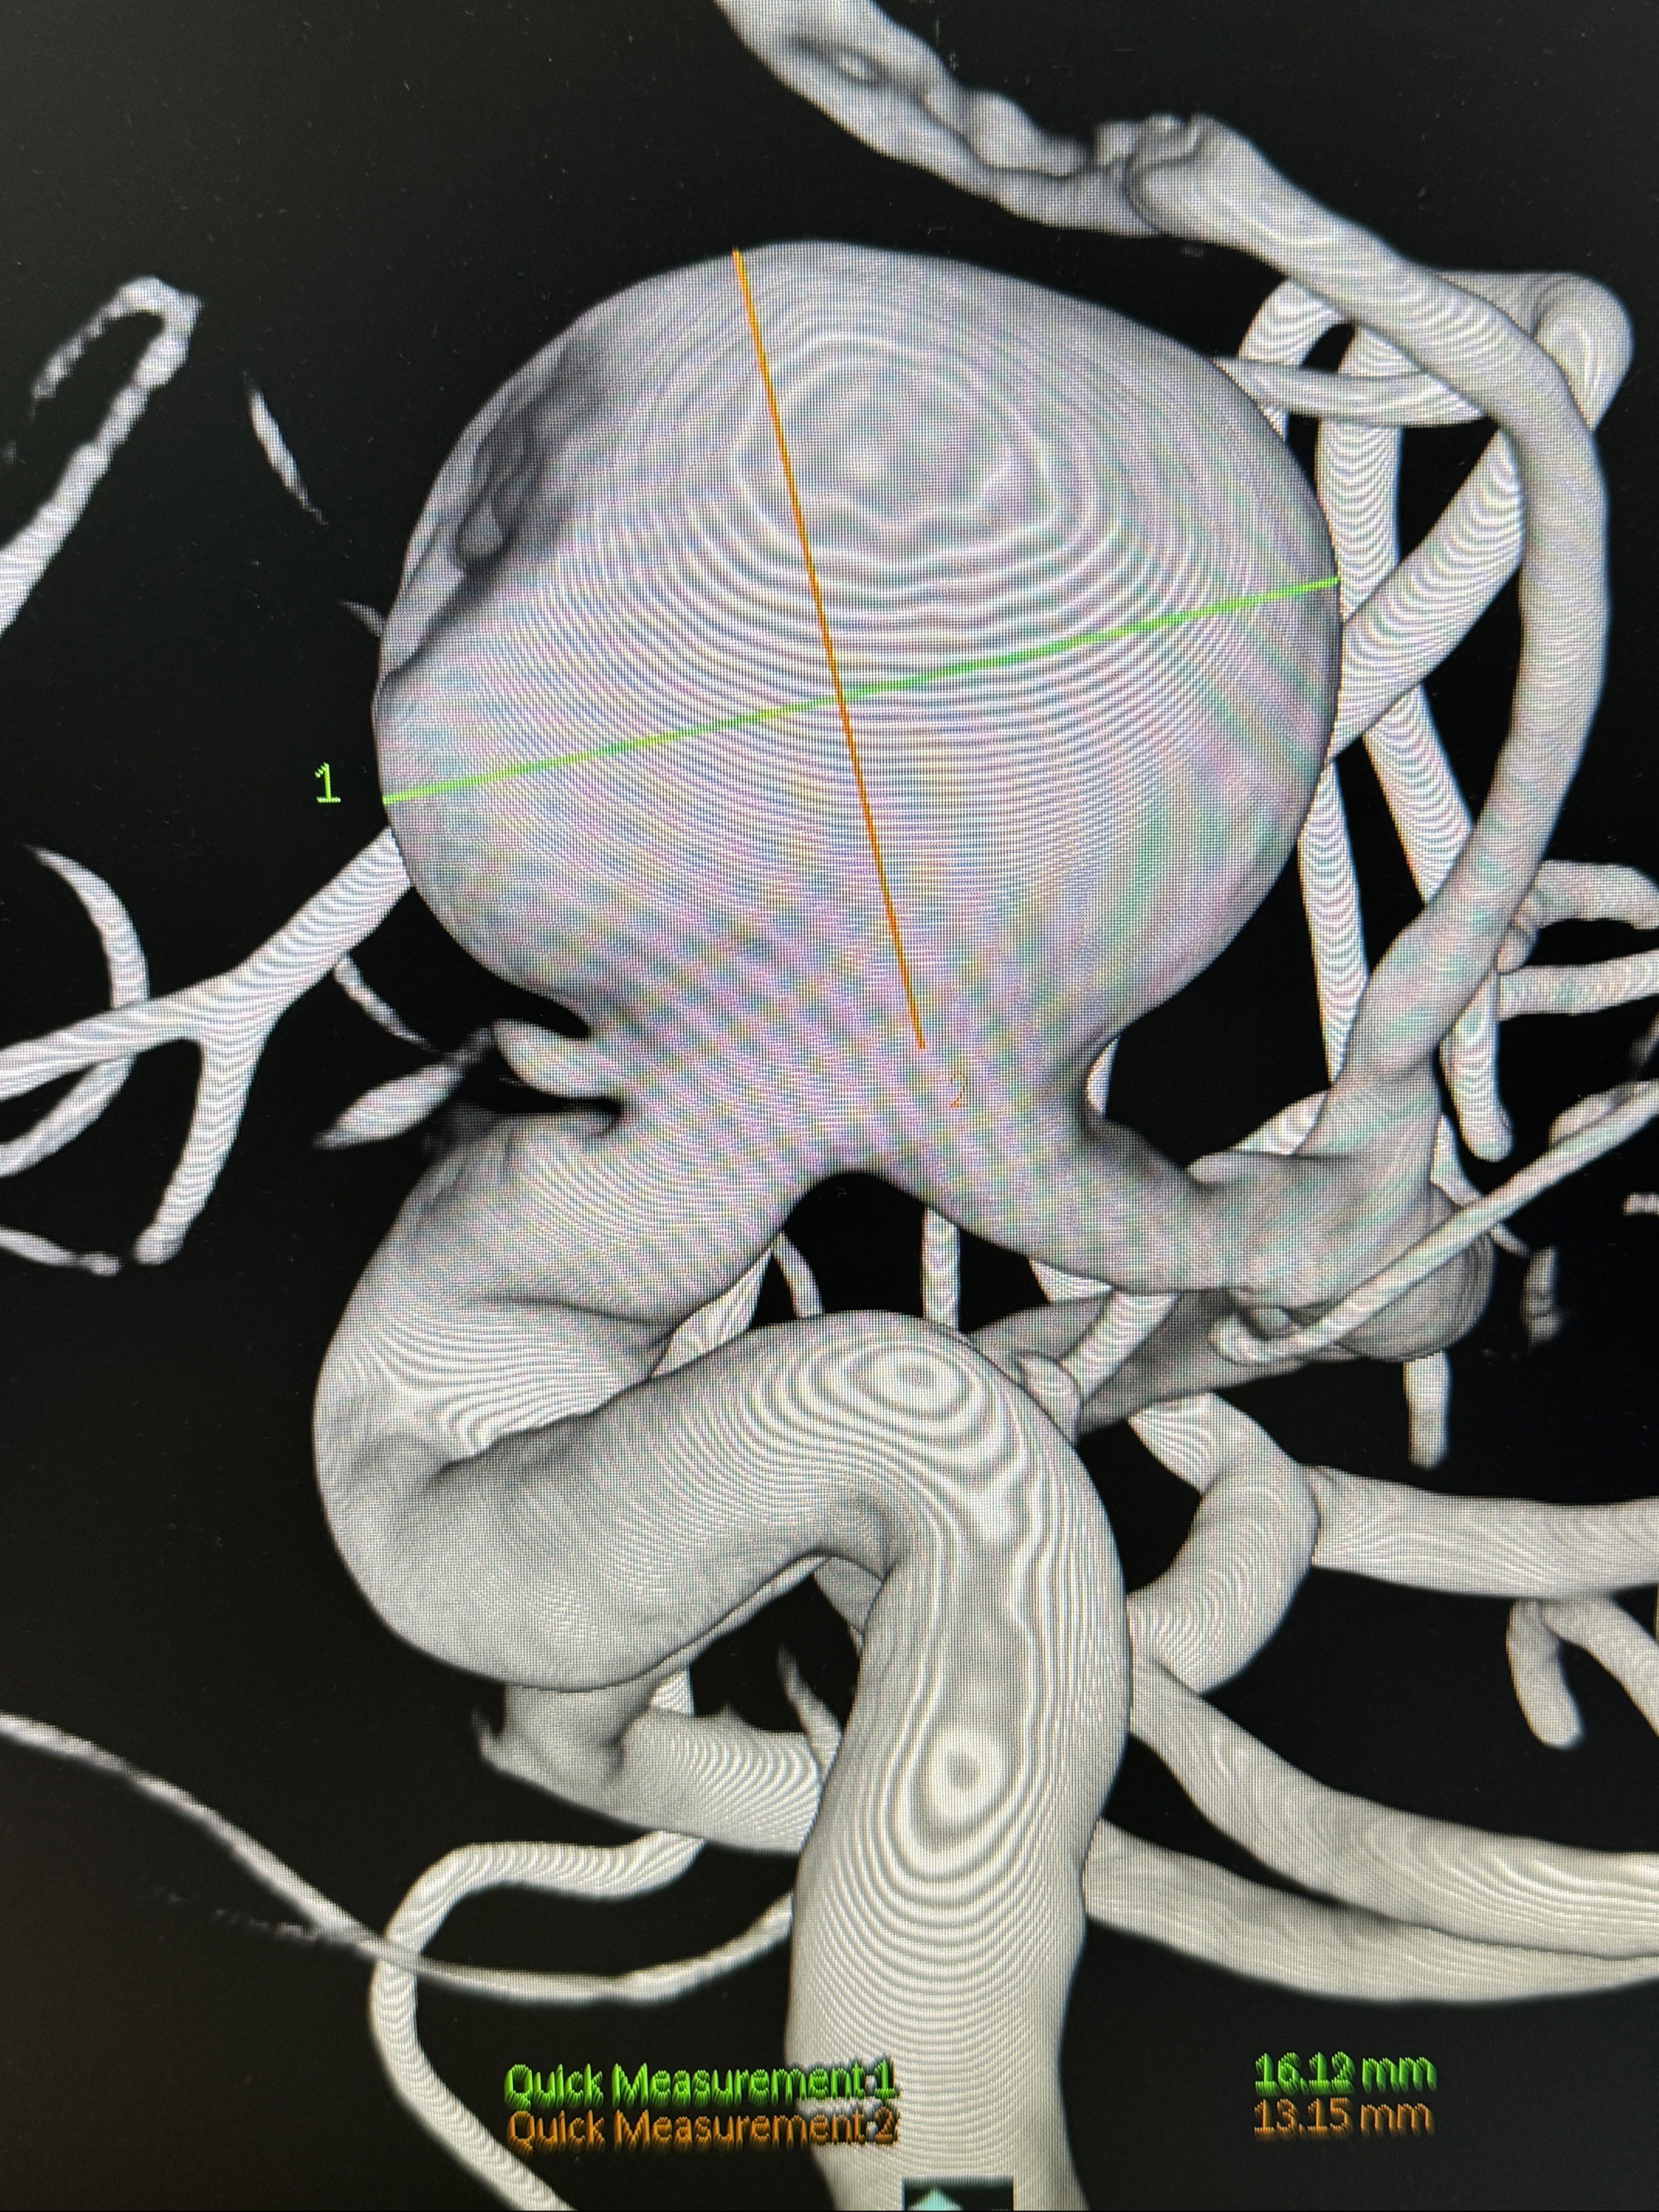

旋转3D展示动脉瘤局部的血管构筑

测量动脉瘤的大小:16*13.8*7.6mm大小,较原先变大,考虑双抗后瘤内血栓溶解可能